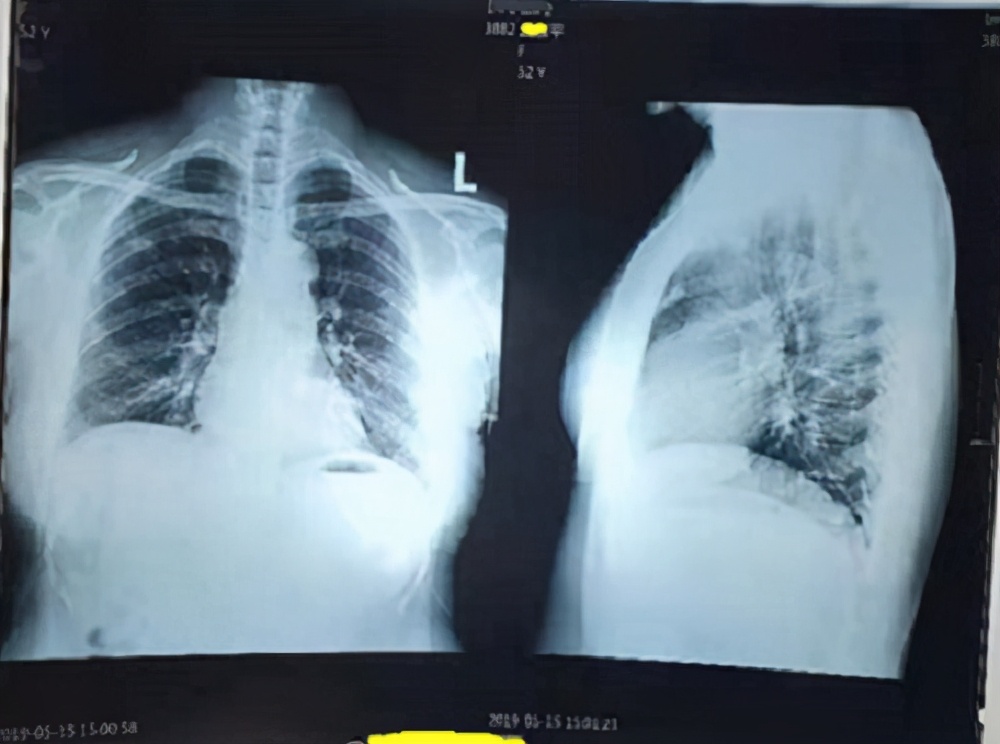

Ms. Ping, 53 years old, had a DR film taken on May 15, 2019, which revealed a nodule in the upper lobe of the right lung.

I then prescribed her the traditional Chinese medicine formula for lung nodules that I discussed in my video, which included ingredients like Gallus gallus domesticus (chicken gizzard) and scorched triple digestants to aid digestion and appetite. Four days after taking the medicine, her symptoms of chest tightness, bloating, and discomfort when breathing gradually lessened. After taking the medication for a month, she experienced no symptoms at all, believed she was cured, and thus stopped taking the medicine and did not undergo any follow-up imaging.

By late October 2019, she again experienced some chest tightness and coughing, so she came to see me for a pulse diagnosis.

I advised her to get another X-ray. On October 28, 2019, she underwent another DR scan, with the imaging findings showing a patchy nodular proliferative focus in the right upper lung lobe.

Although she interrupted the medication for four months after taking it for a month, the report on her follow-up imaging showed improvement at the lesion site.